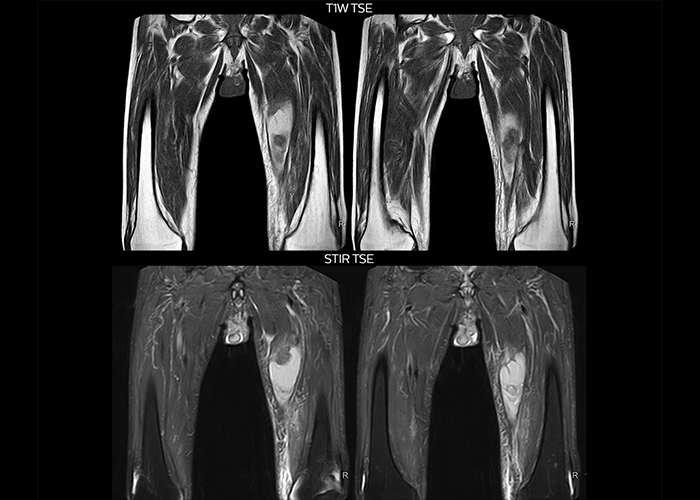

“To avoid coil changes we plan examinations of similar anatomies back to back, such as head and spine. Multiva helps us here a lot because coils don’t need to be changed frequently. Moreover, thanks to parallel imaging technology and 16-channel HeadSpineTorso and 8-channel MSK coils we are able to achieve excellent image quality. In this way Multiva helped us to increase both image quality and productivity.”

“Neurological cases, such as brain and spine imaging, represent the largest share in our MR scanning, followed by musculoskeletal cases. In general, we use simple and basic imaging protocols. But occasionally, we use advanced techniques for problematic cases if necessary.

“Most important, Multiva satisfies our clinical imaging needs very well,” says Mr. Tuna. “Many features of Multiva have become similar to the Ingenia system. Even in more complex imaging such as abdominal and cardiac, the image quality and performance of Multiva is better than we expected. General surgeons and physicians from our hospital’s internal medicine department prefer to refer to us because of this.”